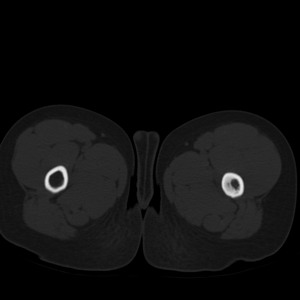

标题: PED1884:患者,男性,7岁。因右髋疼痛5天,而来院检查。 [打印本页]

标题: PED1884:患者,男性,7岁。因右髋疼痛5天,而来院检查。

因右髋疼痛5天,而来院检查。

我们考虑:1、骨皮质增厚症。2、畸形性骨炎。3、骨纤。

右髋疼痛,左侧病变,看来无症状。

支持左股骨上段骨纤维异常增殖症可能性大.

考虑左股骨上段骨纤维异常增殖症。